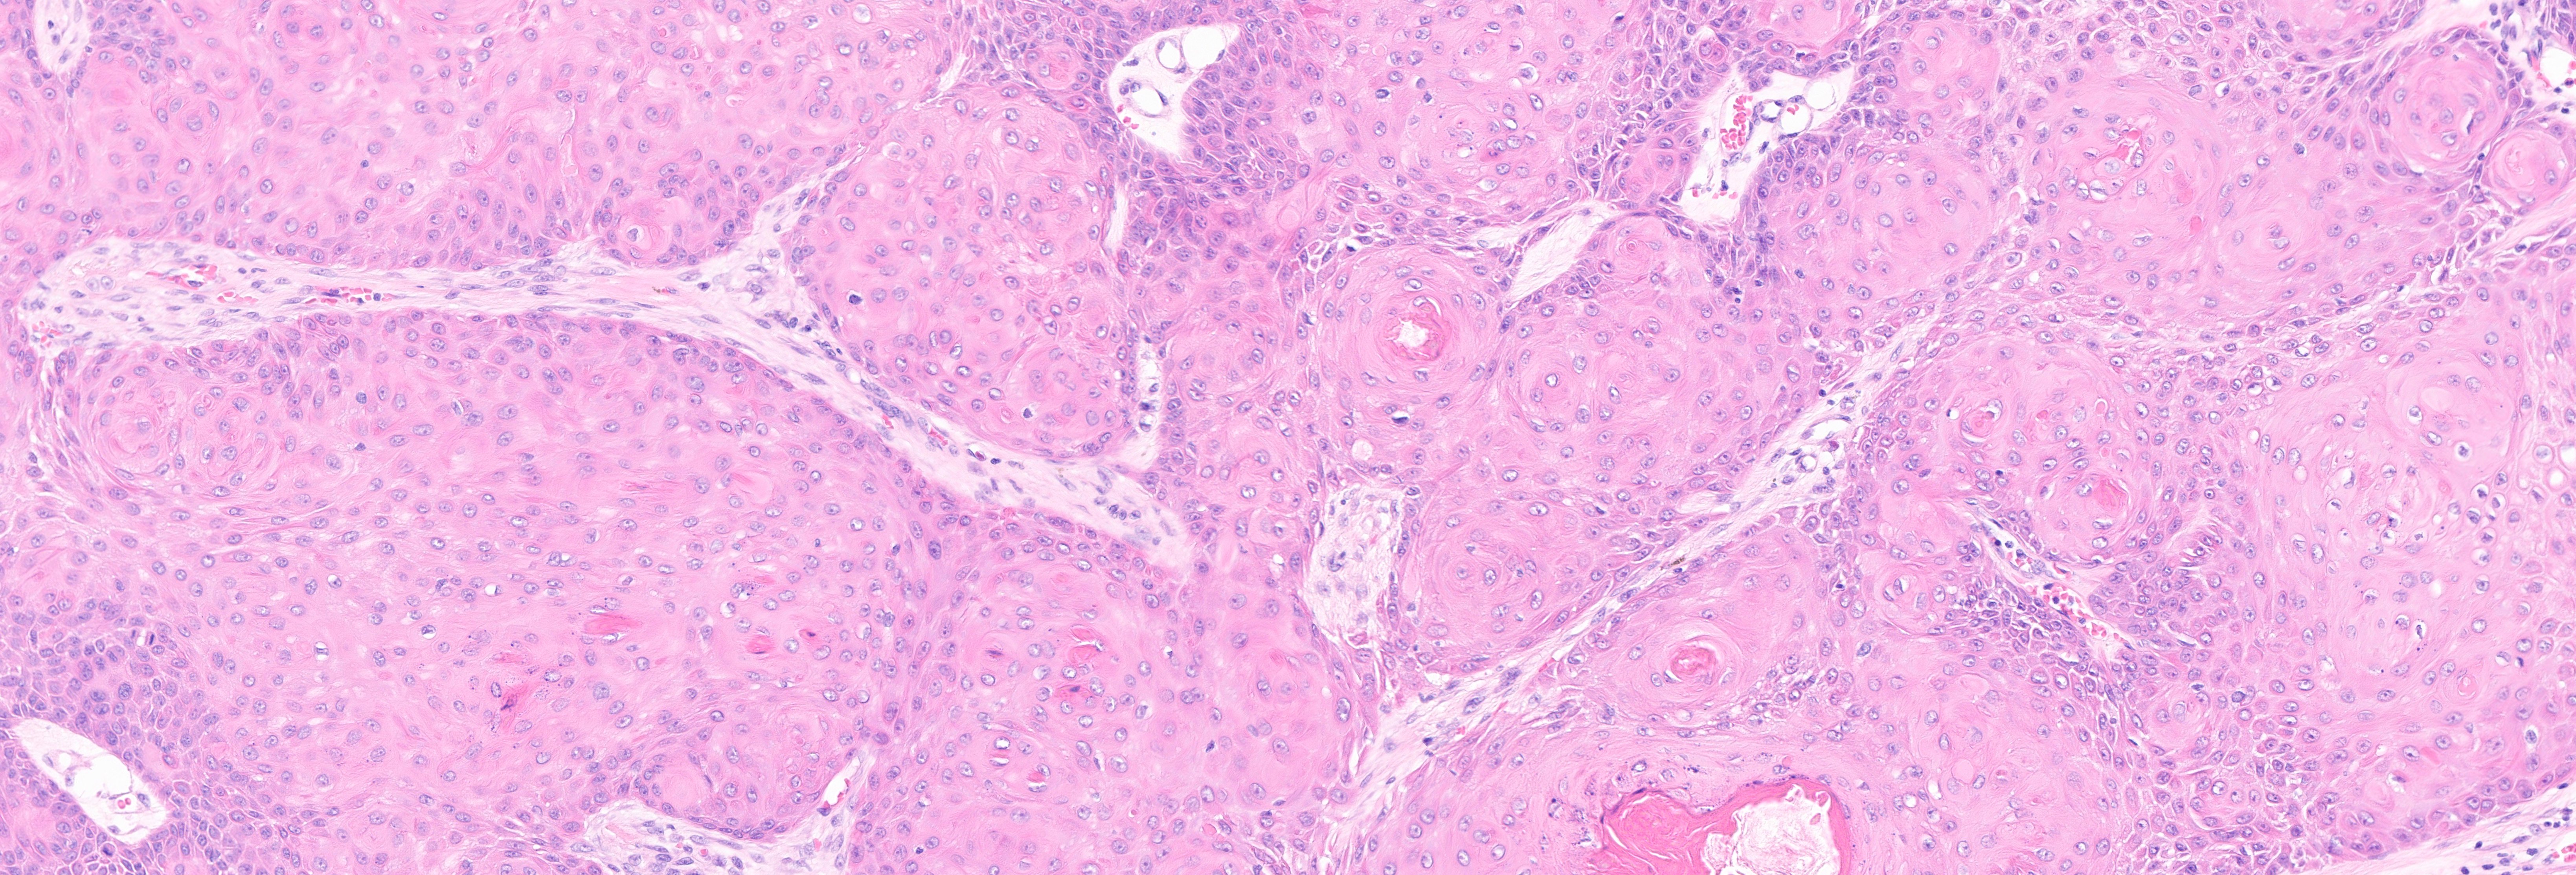

Expert microscopic examination of skin tissue serving dermatologists across Indiana and the Midwest with guaranteed 24-hour turnaround for routine cases.

Melanoma & skin cancers

Inflammatory skin diseases

Autoimmune skin disorders

Nail & hair pathology

and more...